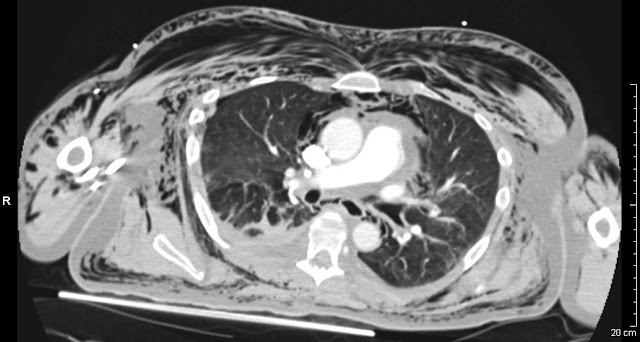

The final crazy story I have from this rotation was a 15yo boy who came in after playing paintball. He had taken off his helmet to wipe the fog from the visor, when a paintball nailed him in the eye. When I saw it was swollen to the point where it couldn't open even when i tried to pry it open. THe poor kid was in shock I think, because he didn't really know what was happening. We got a CT scan to see what was going on and we noticed that the normal bulge of the eye wasn't there. And sure enough, the eyeball had ruptured, we call it a globe rupture. There is very little likelihood that he will ever be able to see out if it again. They took him to surgery to see if they could save it. This case was especially memorable for me, because I had to tell the parents what happened and that their son would most likely not have 2 eyes. Last I heard, the surgeons were discussing glass eyes with the parents.